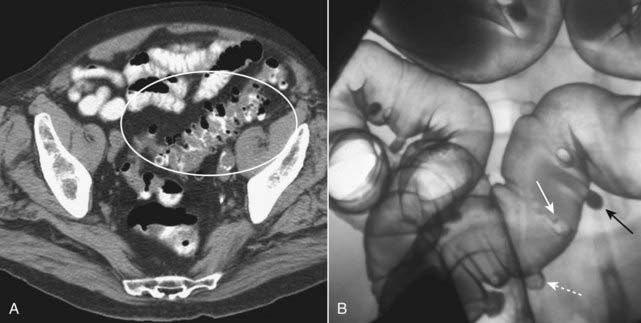

image They occur most often in the sigmoid colon and are readily identified on either barium enema or CT examination as small spikes or smoothly contoured collections of air or contrast attached to the colon (Fig. 18-13).

image

Figure 18-13 Diverticulosis.

A, In this CT scan of the pelvis, diverticula contain air and appear as small, usually round outpouchings, especially in the region of the sigmoid colon (white oval). B, There are numerous outpouchings containing barium seen in the sigmoid colon of this air-contrast barium enema examination. Some diverticula are filled with barium (solid black arrow), while others contain air and are outlined with barium (dotted white arrow). Where a diverticulum is seen en face, it produces a circular density (solid white arrow), which can mimic the appearance of a polyp.

imageCT findings of diverticulitis start with the presence of diverticula and include thickening of the adjacent colonic wall (>4 mm); pericolonic inflammation—hazy areas of increased attenuation or streaky, disorganized linear and amorphous densities in the pericolonic fat; abscess formation—multiple small bubbles of air or pockets of fluid contained within a pericolonic soft tissue, masslike density; and perforation of the colon—extraluminal air or contrast either around the site of the perforation or, less likely, free in the peritoneal cavity (Fig. 18-14).

Figure 18-14 Diverticulitis, CT.

A, Infiltration of the pericolonic fat is demonstrated by a hazy increase in attenuation (solid white arrow) of the normal fat. Focal infiltration of fat is a common characteristic of inflammatory disease. B, There is a large abscess cavity (A) in the left lower quadrant in this close-up of a CT scan of the lower abdomen. There are adjacent small bubbles of gas that are not contained within the bowel and infiltration of the normal fat (dotted white arrow). These findings are secondary to a confined perforation with abscess formation from diverticulitis.